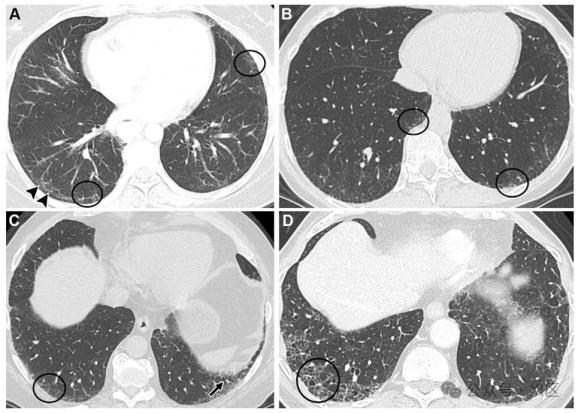

3、两肺间质纤维化的严重程度需综合评估,其危害程度因个体差异而异,总体上可能从轻度影响生活到危及生命,需通过医学手段动态判断并规范管理影像学表现是判断严重程度的核心依据胸部高分辨率CT可直观显示肺部病变程度轻度间质纤维化仅表现为肺部纹理增多或网格状阴影,提示纤维化处于早期阶段而重度病例。